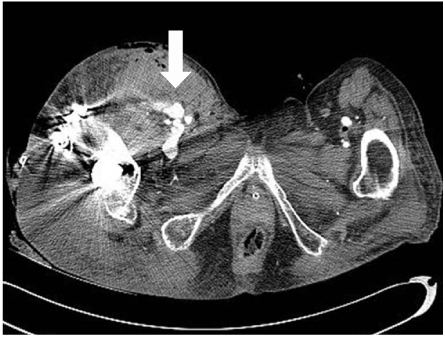

Fig. 2

Clinical photograph of thigh swelling with knee flexion contracture. Notice the swelling of injured limb is more than twice the circumference of the contralateral limb.

An 82-year-old woman, previously in bedridden state due to general weakness, was brought to the emergency department by guardians with right hip pain and severe thigh swelling. She was hospitalized at local hospital for 2 years and during stay, only sitting position was possible. Two weeks prior to our hospital visit, she had a history of fall-down from bed but was neglected. The radiographs demonstrated a subtrochanteric hip fracture (Seinsheimer classification grade 2b) with abrupt angulation of the proximal fragment and artherosclerotic vessel (Fig. 1). Additional findings included 30~40 degrees of flexion contracture of knee with severe swelling of the injured limb, more than twice the circumference compared to the contralateral limb (Fig. 2). There were ecchymoses in the anteromedial aspect of the right proximal thigh. The femoral and pedal pulses were symmetric and palpable in both lower limbs. On admission, the blood pressure was 100/80 mmHg with the heart rate of 90 bpm. The initial hemoglobin was 9.5 g/dl with the hematocrit of 0.22. The patient was managed with Buck's traction overnight. She was taken to the operating room the next day and gently placed on the fracture table under spinal anesthesia. The proximal fragment was severely abducted, externally rotated and flexed, making the nail entry into the greater trochanter difficult. Small (3 cm) incision at greater trochanter level was made in order to insert the reduction clamp. Large amount of hematoma was evacuated right after deep fascia incision. Reduction clamp was placed through an incision to reduce the proximal fragment prior to nailing. But, soon after the reduction against the deforming force, active bleeding was observed. The bleeding point was unidentifiable due to massive bleeding and inadequate operative field. Vital sign became unstable with systolic blood pressure dropping to 50 mmHg. Massive gauze packing on the suspected bleeding site was done with rapid intramedullary nail insertion (Proximal Femur Nail, Synthes, Davos, Switzerland). Skin closure and compressive dressing was performed to stabilize the vital sign. Popliteal and pedal pulse was weak. In order to identify the injured vessel, computed tomographic angiography was performed, and active bleeding in one of the branch vessel of right deep femoral artery was suspected (Fig. 3). To further evaluate the injured vessel, emergent digital subtraction angiography was performed. At first, the left common femoral artery was punctured by using a Seldinger technique. Extravasations of contrast medium was identified on the extremity angiogram, originating from one of the minor proximal branch of right deep femoral artery, while filling a 2 cm sized pseudoaneurysm (Fig. 4A). At this stage, coil embolization was attempted to stop the ongoing bleeding. The suspected branch of right deep femoral artery was superselected by using a 2.4 Fr microcatheter (Progreat, Terumo, Tokyo, Japan). Via the microcatheter, attempts were made to completely embolize the injured artery with 13 platinum-made microcoils (Tornado®, Cook Inc., Bloominton, Minnesota, USA), including four 6/2 mm, one 5/2 mm, six 4/2 mm and two 3/2 mm microcoils. Immediately after the embolization procedure, digital subtraction angiography was performed. The angiograms demonstrated complete occlusion of the feeding vessel and the cessation of the active bleeding (Fig. 4B). No other branch except the injured terminal branch was occluded on the angiogram. The day after embolization, the packed gauze was removed surgically.

Fig. 2 Clinical photograph of thigh swelling with knee flexion contracture. Notice the swelling of injured limb is more than twice the circumference of the contralateral limb.